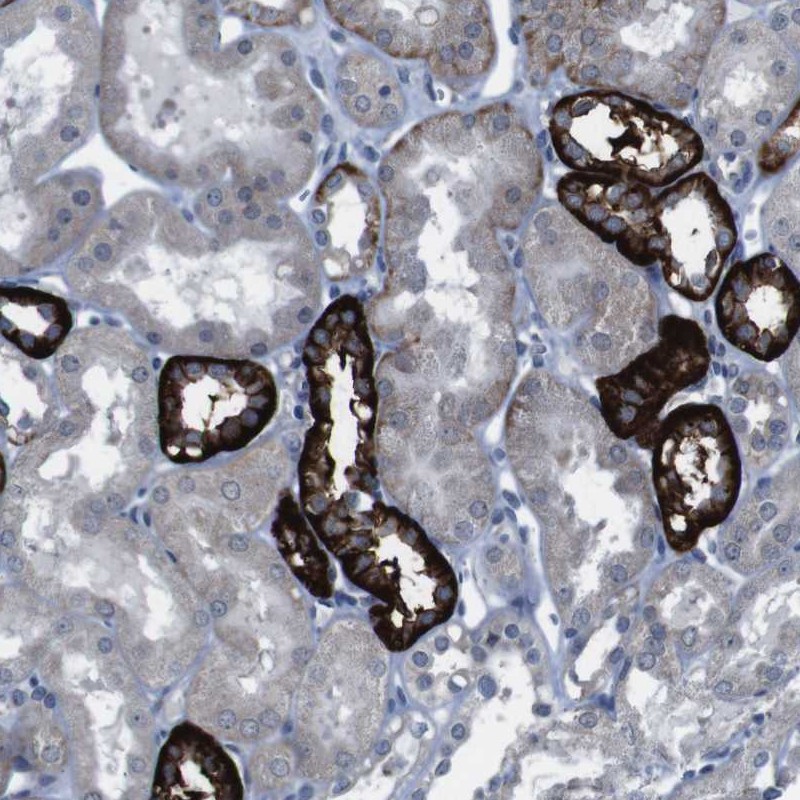

Immunohistochemical staining of human kidney shows strong cytoplasmic positivity in a subset of cells in tubules.